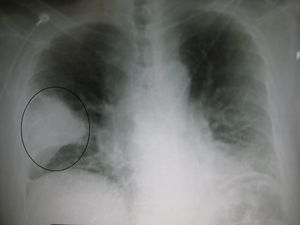

A Xray showing a white wedge in the right lung field of a chest X-ray.

A chest X-ray showing a very prominent wedge shaped pneumonia in the right lung.

Pneumonia as seen on chest x-ray. A: Normal chest x-ray. B: Abnormal chest x-ray with shadowing from pneumonia in the right lung (white area, left side of image).